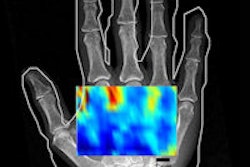

Slowly but surely, PET/CT is gathering clinical momentum, it seems. Further evidence of the technique's potential for changing patient management decisions comes this month with the publication of a new U.K. study of recurrent malignant melanoma. Used via referral from a specialist skin cancer multidisciplinary team, FDG-PET/CT can become a very valuable tool, the authors believe. Get the story here.

Support is also growing for FDG-PET alone, however. Another recent study found the technique changed the management plan for more than one-third of patients with Merkel cell carcinoma, and altered disease stage in approximately one in five cases. With the information provided by FDG-PET and subsequent changes in treatment plans, overall survival for Merkel cell carcinoma patients was 60% after three years and 51% after five years. To read more, click here.

Meanwhile, preliminary research conducted in Naples, Italy, and the U.S. concluded that FDG-PET/MRI more accurately evaluated and more often changed the management of patients with various forms of cancer in a comparison with PET/CT. The researchers found PET/MRI outperformed PET/CT for swollen lymph nodes and tumors in regions that were difficult to assess with PET/CT, such as the kidneys, and achieved greater sensitivity with bony and hepatic metastases. Click here for the details.